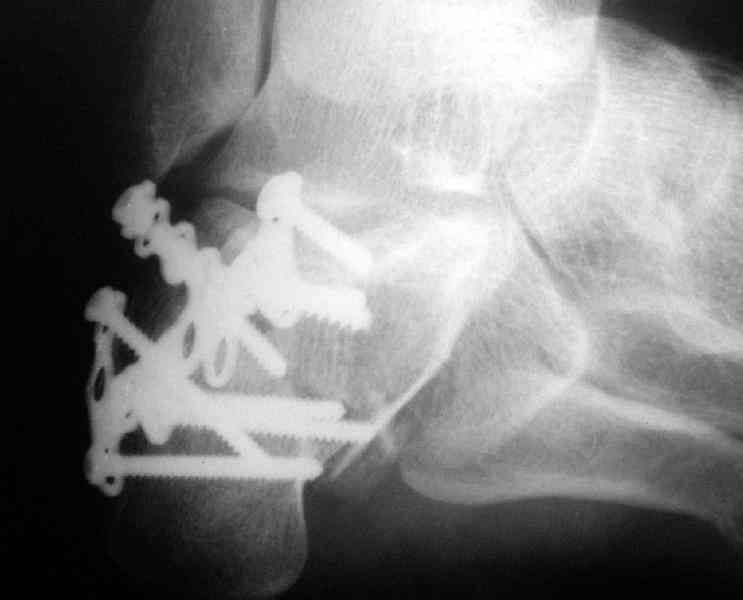

Re: Перелом пяточной кости

Какой предпочитаете доступ? Нет ли показательных рентгенснимков?

Открытый и закрытый способы лечения.